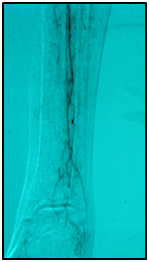

An example: A 77-year-old, diabetic woman, complaining of rest pain in her left leg and carrier ulceration on the left hallux. The physical examination showed absence of distal pulses in her left leg. Color Doppler ultrasound performed before treatment confirmed BTK critical lesions with no patency and a diagnosis of CLI.

Endovascular procedure was done with antegrade access in the ipsilateral common femoral artery, diagnostic angiography confirmed: Patency of the femoral-popliteal axis, occlusion of the posterior and anterior tibial arteries, two critical stenotic lesions in the fibular artery and revascularization of the dorsalis pedis and plantar arteries by the fibular artery. To treat the fibular critical atherosclerotic lesions were performed a percutaneous transluminal angioplasty using a 0.0018in.guidewire, catheter support and a catheter balloon (3,0x6 mm and 3,5x 15mm).

Final angiographic control showed patency of the fibular artery and dorsalis pedis, with direct flow for the first metatarsal artery, thus guaranteeing enough flow to heal the ulcer in six months after the procedure. In conclusion endovascular treatment has a high technical eligibility with good reported outcomes and represents an alternative for diabetics with CLI Disease (Figure 1 and 2).

• Figure 1 Angiography from left to right showing femoral-popliteal axis, occlusion of the posterior and anterior tibial arteries, in detail two critical stenotic lesions in the fibular artery.